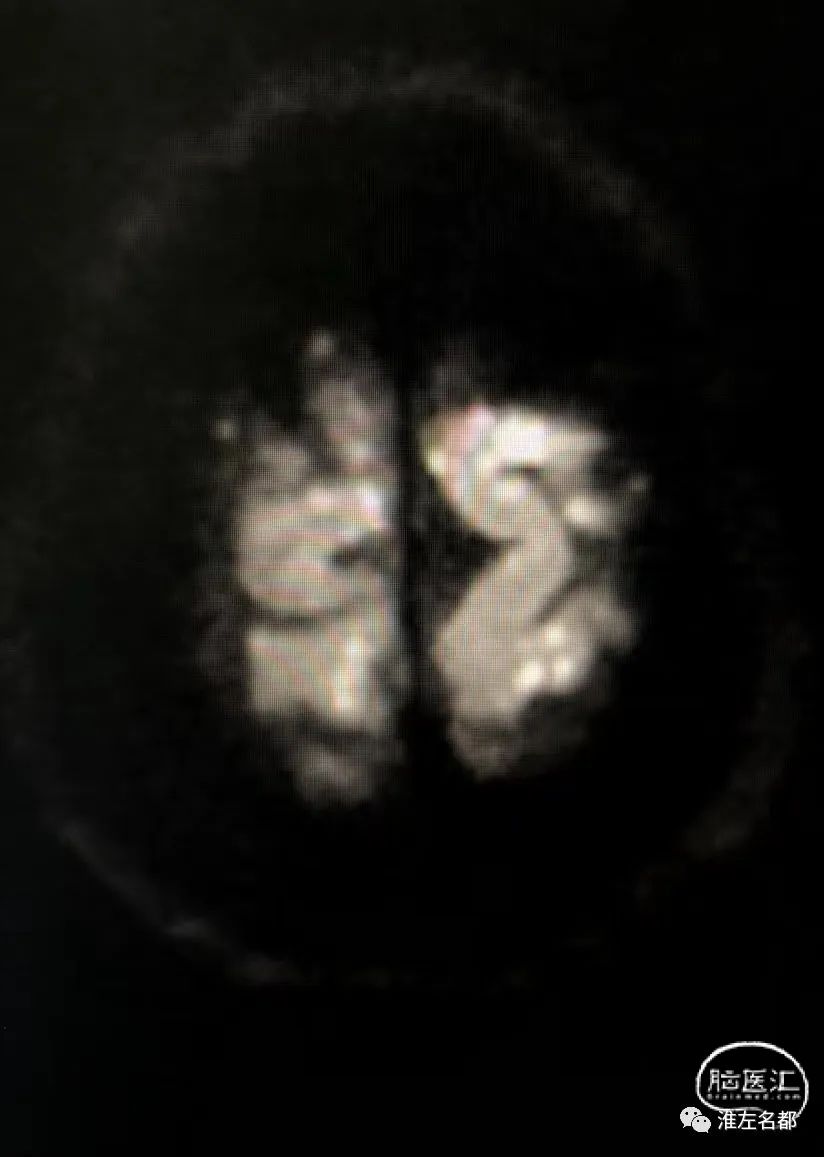

脑DWI:双侧半球皮质和皮质下弥漫分布的点状急性微小梗死灶。